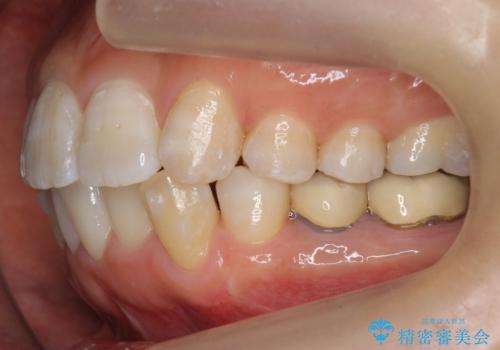

奥歯を後ろに下げて、前歯を並べています。

マウスピースと矯正用のミニスクリューを使用して治療しています。

銀歯も白くということでしたので虫歯治療も一緒に行っています。

左上7の根の治療や左下56銀歯の治療なども行いました。

右下7は根管治療をおすすめしましたが、患者様のご希望により抜歯となり、そのスペースを利用して下の前歯をならべています。